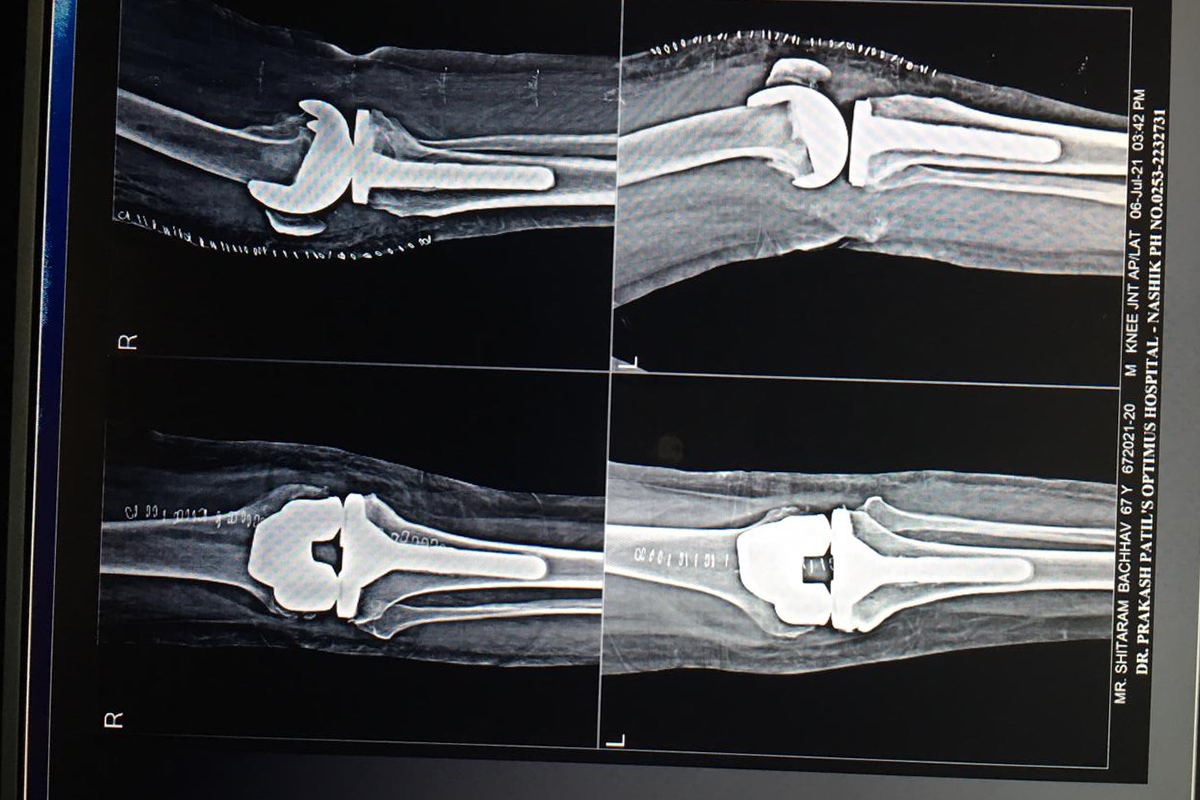

Joint Replacement